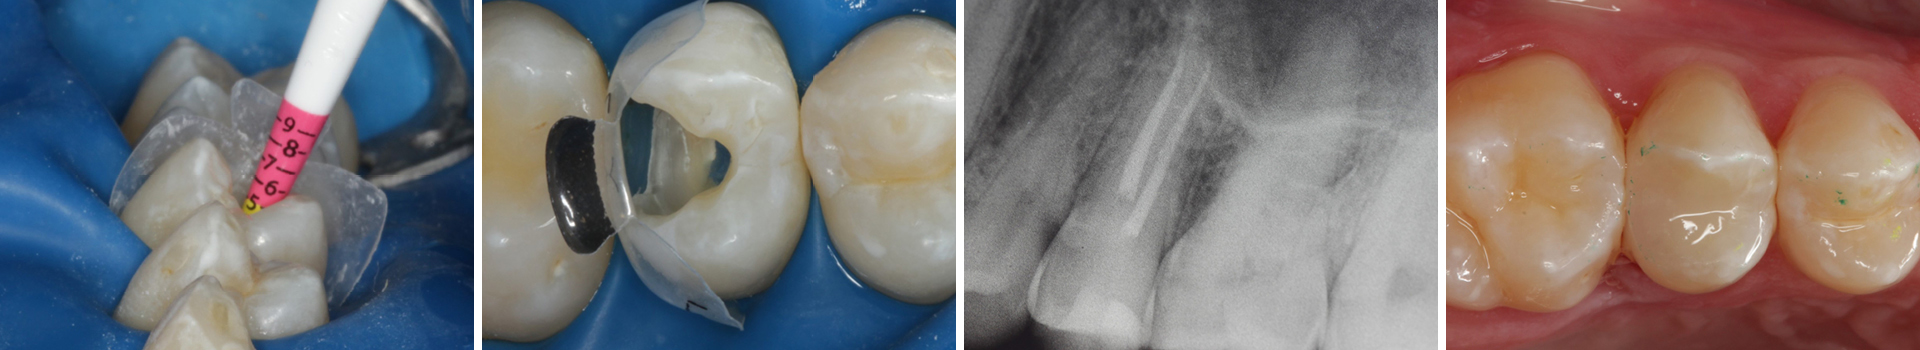

Abbildung 24

Folgesitzung: Trepanation Zahn 25

Abbildung 25

Nadelaufnahme nach elektronischer Längenmessung

Abbildung 26

Wurzelkanäle gefüllt

Abbildung 27

Kontrollröntgenaufnahme

Abbildung 28

Kompositrestauration nach „Schachtverschluß“; keine Krone geplant